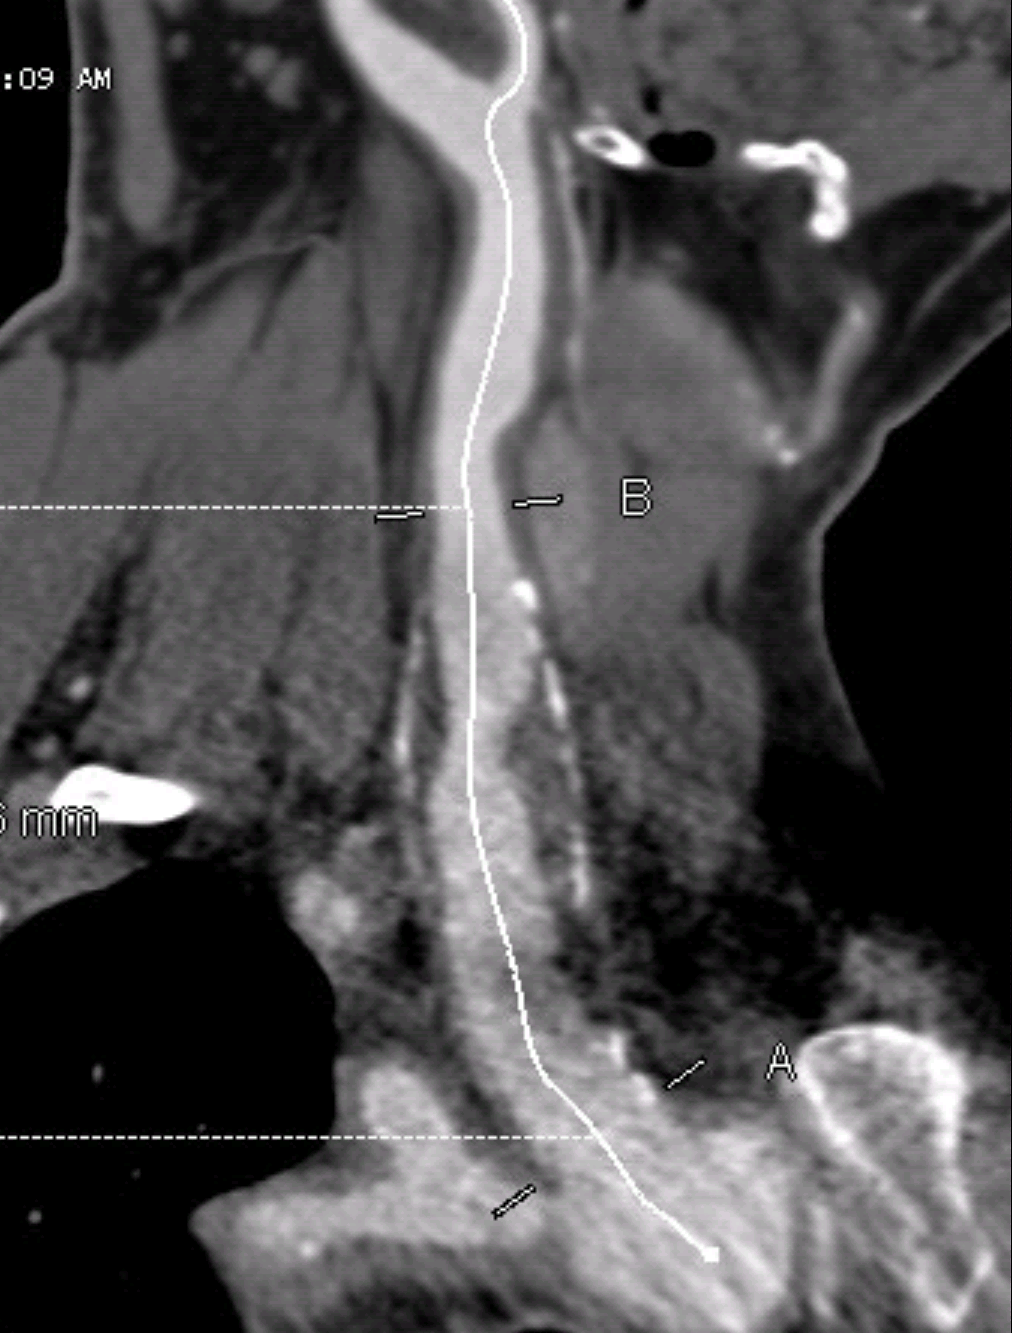

In the operating room, the carotid bifurcation was exposed via an oblique skin line incision with the C-arm oriented on the patient’s right. A table was draped off the patient’s left arm which had been prepped for brachial access for aortography. Access was taken from the distal common carotid artery with orientation of the Rosen wire down the descending thoracic aorta -this was to accomodate the nose cone of the device, a Cook 24mm AUI converter with a 12mm iliac extension. This choice of stent grafts accorded with the type of graft I would have chosen for the open repair (Dacron based), and had the appropriate size to exclude the aneurysm from the short proximal neck to the distal segment. The arteries were surrounded by inflammatory tissues and this made dissection challenging but not onerous as a redo dissection.

The predeployment arteriogram identified fluoroscopic clues to deployment.

In this patient’s case, the tip of the ET tube provided an excellent reference. (see above composite arteriogram).